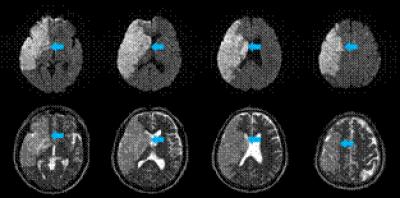

The middle cerebral artery territory comprises the corticospinal tract, which is responsible for fine motor activity of the hands, and the corticoreticulospinal tract, which is involved in postural control and locomotor function, and therefore, motor weakness is one of the most disabling sequelae of a middle cerebral artery infarct. However, little is known about motor outcomes in patients with a complete middle cerebral artery territory infarct. Prof. Sung Ho Jang and colleagues from College of Medicine, Yeungnam University investigated 23 patients with a complete middle cerebral artery territory infarct subjected to comprehensive rehabilitative management, including movement therapy and neuromuscular electrical stimulation of the affected finger extensors and ankle dorsiflexors, for more than 3 months. After receiving rehabilitation treatments for 6 months, the motor function of the lower extremities was found to be better than that of the upper extremities, and about 70% of these patients were able to walk independently, but no patient achieved functional hand recovery. These data, published in the Neural Regeneration Research (Vol. 8, No. 20, 2013), will provide supporting evidence for developing rational rehabilitation strategies and establishing proper goals for stroke patients.

Article: " Motor outcomes of patients with a complete middle cerebral artery territory infarct," by Sung Ho Jang, Min Cheol Chang (Department of Physical Medicine and Rehabilitation, College of Medicine, Yeungnam University, Daegu 705-717, Republic of Korea)

Jang SH, Chang MC. Motor outcomes of patients with a complete middle cerebral artery territory infarct. Neural Regen Res . 2013;8(20):1892-1897.